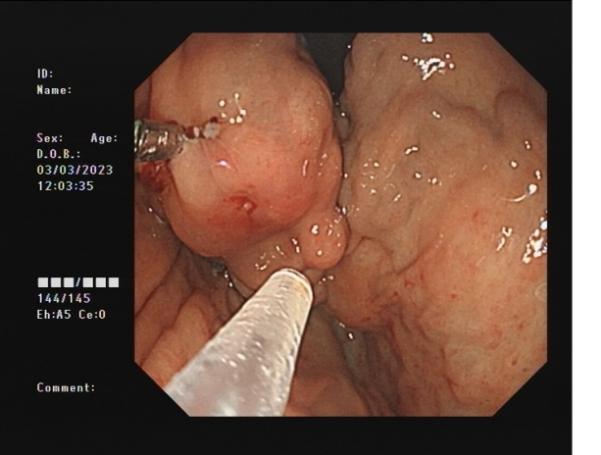

胃底間質瘤 內鏡下全層切除術后創面 切除后標本

內鏡下全層切除術(EFTR):治療消化道黏膜下腫瘤(最主要):起源于固有肌層深層、部分腔外生長、與漿膜層密不可分;少部分抬舉征陰性消化道癌前病變和早期癌;少部分困難解剖部位結腸病變(如結腸憩室內腺瘤)等。